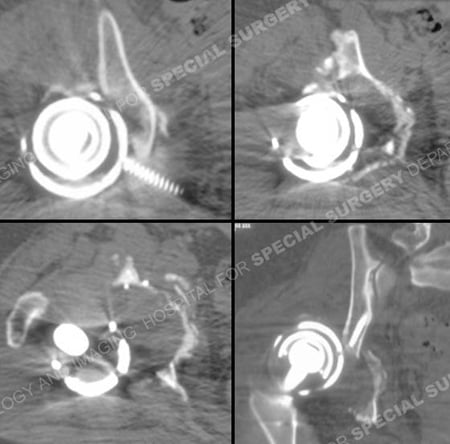

CT scan images further delineating the fracture pattern.